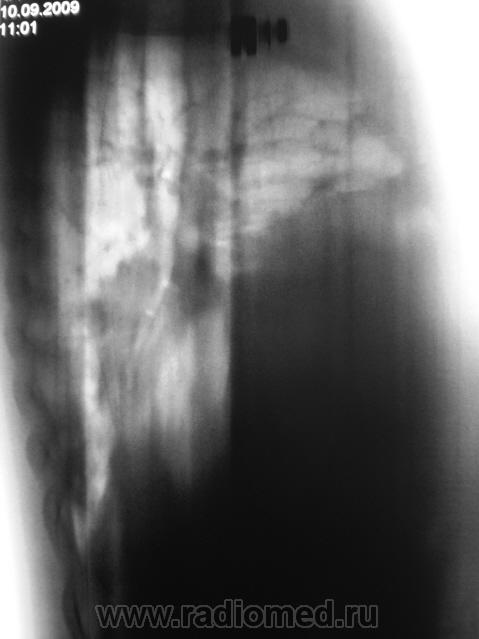

Динамика после проведенного противовоспалительного лечения. Сегодня пациент был доставлен в рентгеновский кабинет для проведения "контроля". Проведена рентгенография в стандартных проекциях - прямая и боковая, был произведен 1 срез в боковой проекции.

Ваше мнение коллеги?